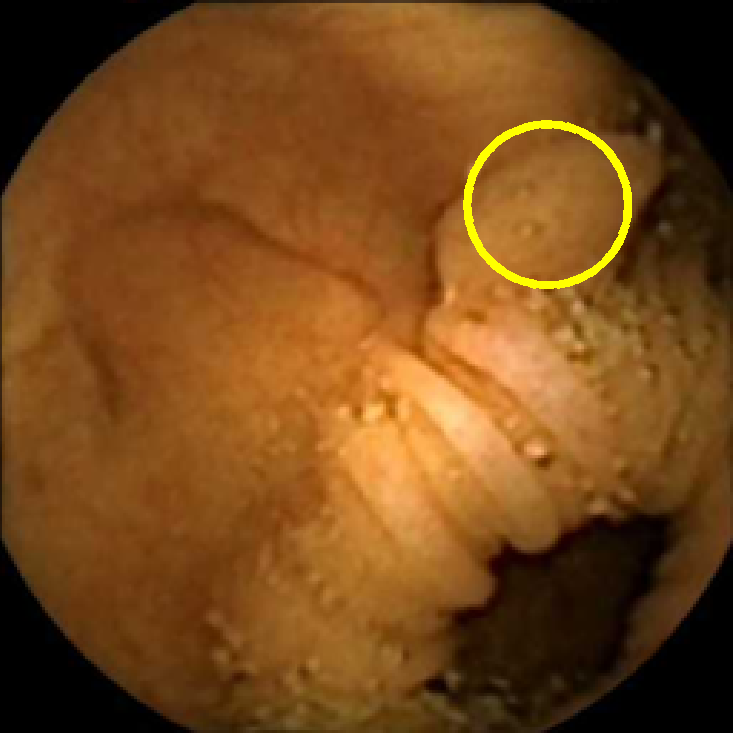

In Figure 5 we show the circles of radius corresponding to the features that were correctly classified as polyps by (29). We observe that the classifier was able to identify the polyps of a variety of shapes even in the presence of small amounts of trash liquid (first row) or when the polyps are located next to mucosal folds (rows two to four in column (c)).